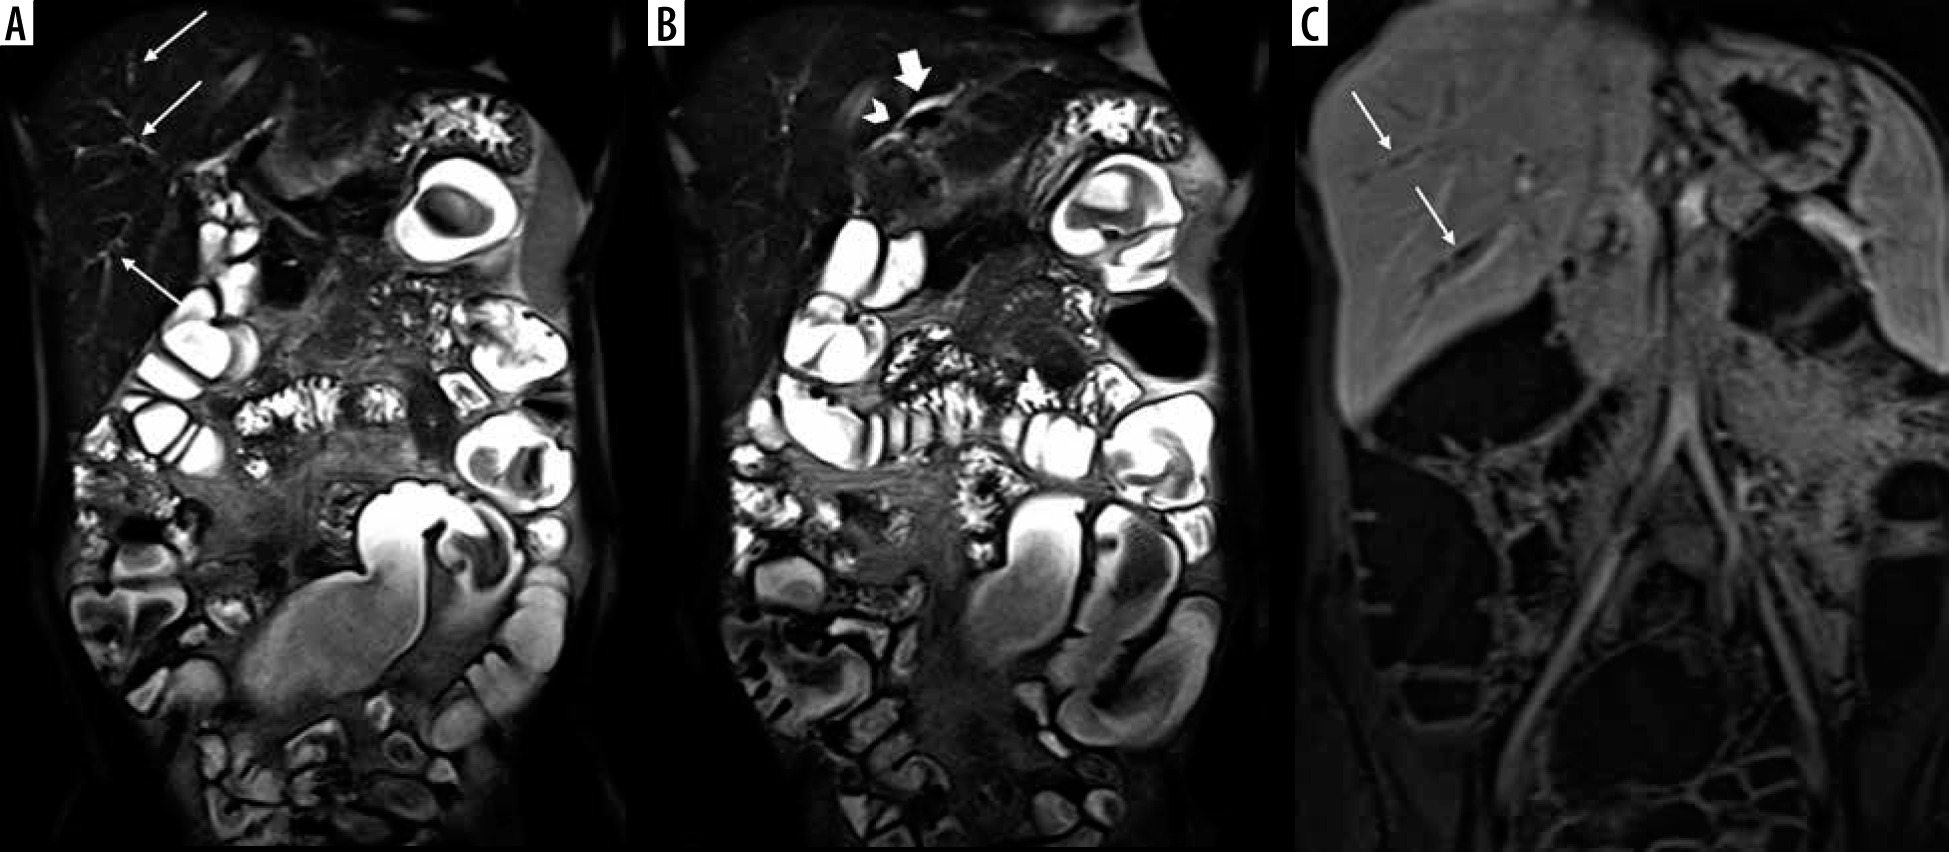

Figure 2

Primary sclerosing cholangitis findings in magnetic resonance enterography of a 26-year-old male patient with Crohn’s disease. A, B) Coronal T2-weighted HASTE images show mural irregularity in intra hepatic bile ducts in segments 6 and 7 (thin arrows) associated with a low-grade stricture (arrowhead) and mild upstream dilation (thick arrow) in segment 2. C) Coronal post-contrast T1-weighted VIBE sequence displays mildly irregular mural thickening and enhancement (thin arrows) in intrahepatic ducts at segment 6 and 7